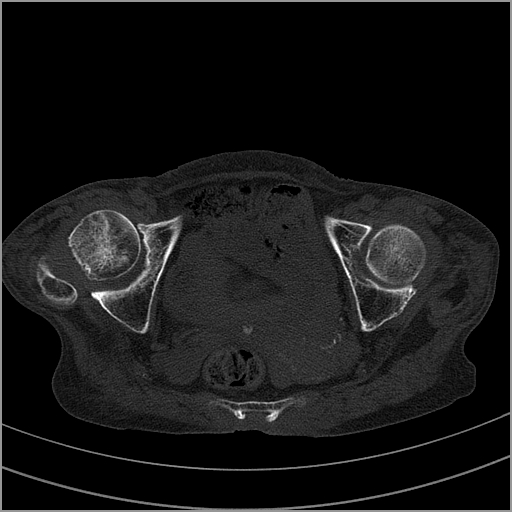

以下是引用老爱克斯新网客在2009-2-3 19:42:00的发言:[br]右侧髋臼及右侧股骨头可见明显骨质破坏,以溶骨性破坏为主,无明显硬化,髋关节间隙变窄,周围软组织明显肿胀,密度不均,脂肪间隙消失。[br] 诊断:右侧髋关节感染性病变,右侧髋关节结核的可能大。[br] 鉴别诊断:1.股骨头缺血坏死,单纯股骨头缺血坏死病例不会累积髋臼骨破坏。2。退行性关节炎,以骨质增生为主,伴有关节面硬化,骨质破坏呈多发小囊状破坏为主,其周围可见硬化环。3.股骨头缺血坏死晚期(第四期)骨质破坏可伴髋关节退行性变,可有骨质增生,但此时骨破坏以股骨头破坏为主,不应该伴有髋臼骨质破坏,因为股骨头的骨破坏是因血运中断,而没有髋臼的血运中断,又没有细菌的感染,怎么能造成髋臼的骨破坏呢。